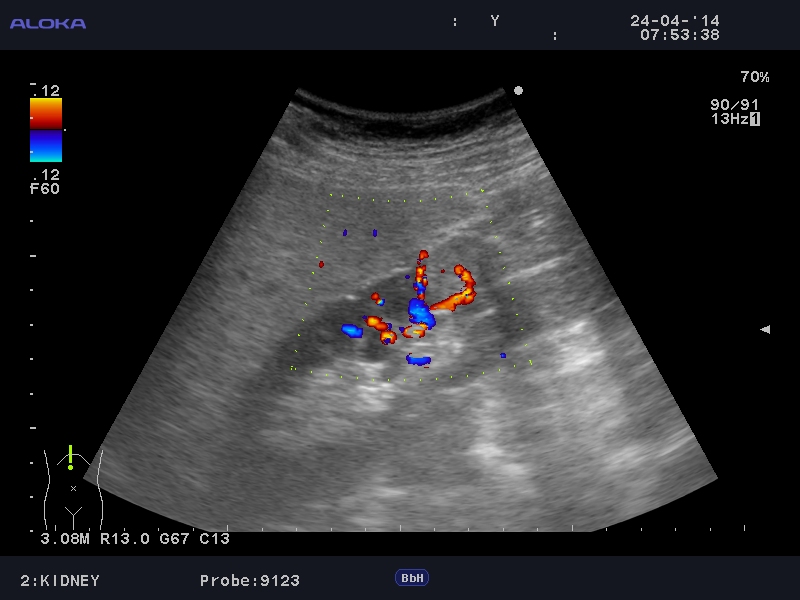

Онкоцитома почки - УЗИ

Женщина 76 лет. Жалоб не предъявляет.

Renal oncocytoma